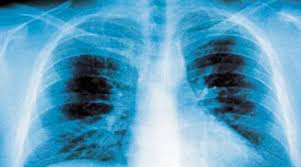

التهاب الرئتين من الأمراض الشائعة

المصاحبة لقدوم البرد حيث يصاب الآلاف بهذا المرض الذي كان قاتلا فيما مضى، ولكن رغم تحسن اكتشافات المضادات الحيوية فإن كثيرين ما زالوا يضطرون لدخول المستشفى للعلاج منه.